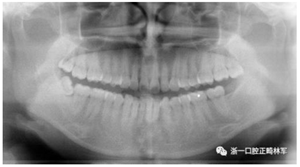

X線片檢查分析

初診全景片:牙齒數(shù)目形態(tài)未見異常,牙根未見異常。48近中阻生。

初診張閉口關(guān)節(jié)片:張閉口位關(guān)節(jié)間隙正常。雙側(cè)髁突外形正常,骨皮質(zhì)連續(xù),未見明顯吸收變形。